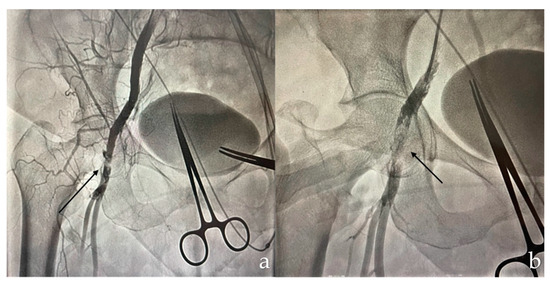

2. Detailed Case Description